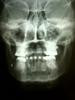

Летом, в июле, мой снимок показал наличие чего-то... По просьбам - выкладываю )

узнала, что в поликлинике по месту жительства работает сын супер врача-хирурга. долго не думала, записалась. осмотр ->приходите со снимками. ну я что-то долго рассказываю. вот снимки новые.

"это кусок блаблаблической фрезы. боюсь, я не полезу туда. есть вероятность, что он в щеке, около щёчной артерии и лицевого нерва. мне туда нельзя лезть, это общая хирургия. "

Хорошо, что все хорошо закончилось, а то судя по снимкам эта "пулька" как то активно двигалась по всей щеке, мало ли куда могла залезть, нерв наверно могла задеть....Бе, мне опять в голову лезут плохие мысли.... ПозитиFFFF!

когда мне удаляли 8ку, она слишком держалась за кость, её подсверливали. когда был щелчок, я подумала, что это зуб отсоединился от кости) а нет, оказывается ) в общем отломался этот кусочек и упал к щеке. он не двигался, это просто с разных ракурсов снимки. его хорошо можно было прощупать, потому что он оброс капсулой твёрдой с гноем )